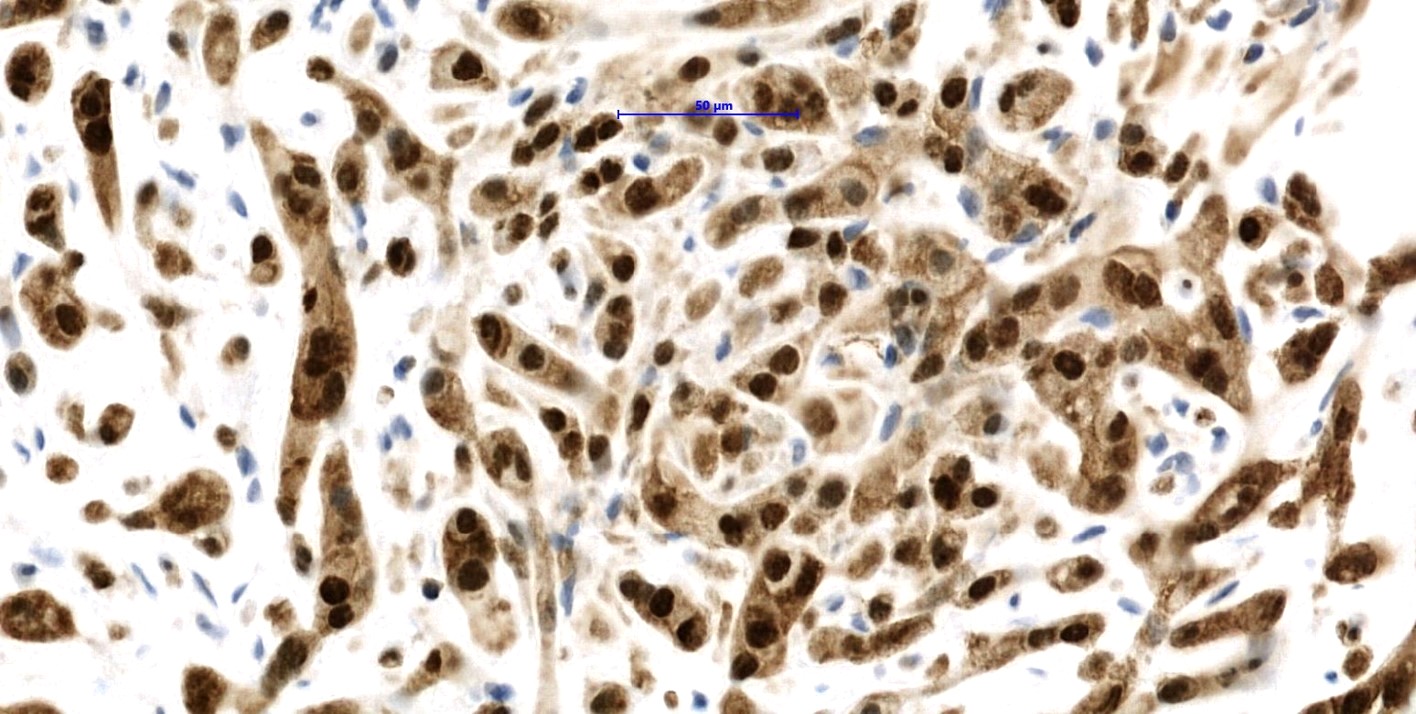

Positive stains

- ERG, CD31, CD34 (can be negative), podoplanin (D2-40), FLI1, von Willebrand factor (Diagn Pathol 2014;9:131, Am J Surg Pathol 1997;21:363)

- CAMTA1 in WWTR1-CAMTA1 rearranged tumors (Am J Surg Pathol 2016;40:94)

- TFE3 in YAP-TFE3 rearranged (less specific) (Genes Chromosomes Cancer 2013;52:775)

Microscopic (histologic) images